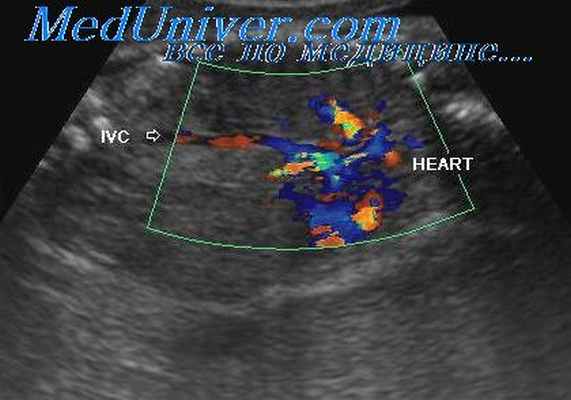

Диагностика

Вена Галена - один из крупнейших венозных коллекторов мозга, который собирает кровь из глубинных отделов обоих полушарий. При наличии мальформации, вена может раздувается до огромных размеров. Заболевание как правило обнаруживают на поздних сроках беременности, когда на рутинном УЗИ плода видят расширенную вену Галена с артериальным спектром кровотока. Для дальнейшего уточнения диагноза и показаний к оперативному лечению может потребоваться МРТ плода.